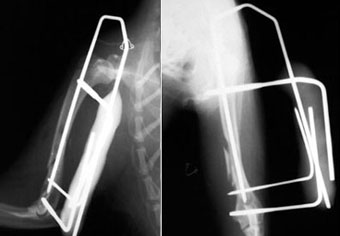

体重1.2kgの猫の脛骨(下腿骨)骨折。

これもピンニングと創外固定をタイインという方法で組み合わせることで、骨折部にメスを入れることなく整復固定しました。

写真上段: 手術前

写真2段目: 手術直後